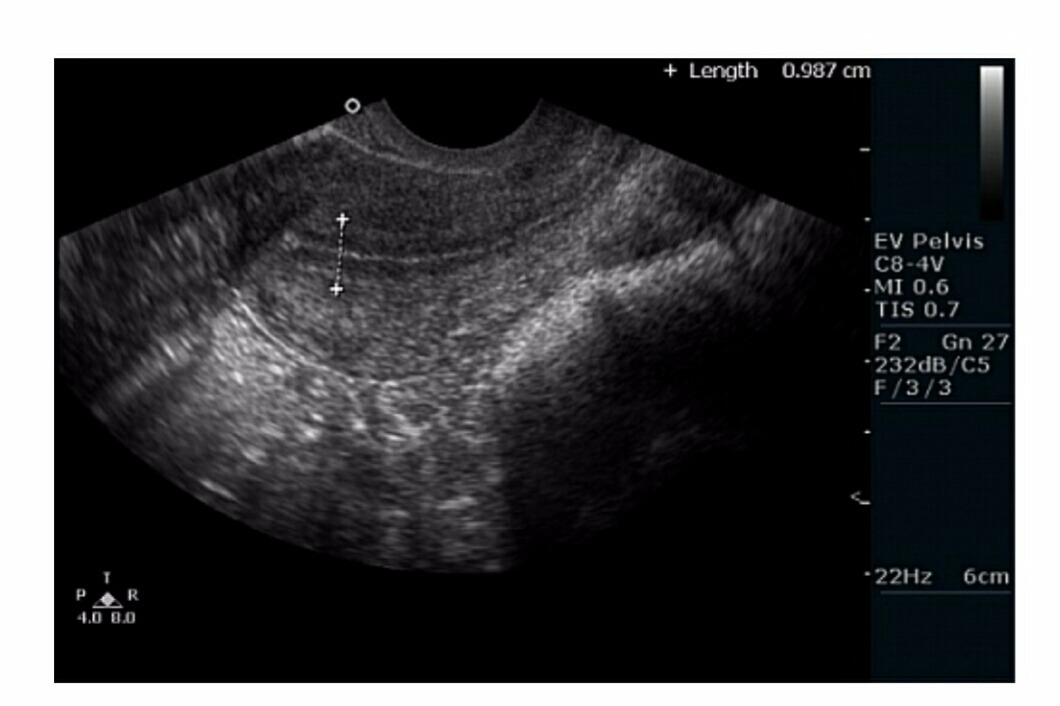

етрия на узи

Утолщения эндометрия на узи 113 фотографий